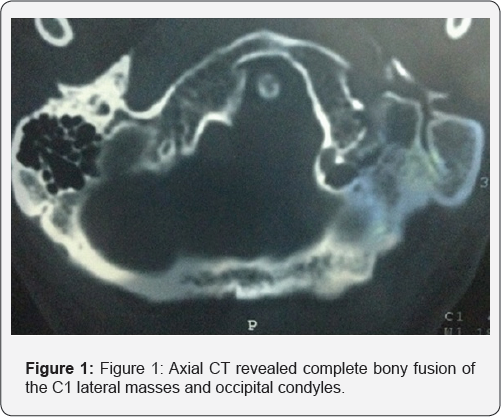

A 34-year-old male presented himself with a one-year history of numbness of all his fingertips in his both hand, hypoesthesia and posterior neck pain. On neurological examination, the patient had marked restriction in the range of motion of the neck in every direction because of low-neck pain radiating to the occipital region. He had no muscular atrophy .Hypoesthesia of both hands. Computed tomography (CT) revealed complete bony fusion of the C1 lateral masses and occipital condyles with reduced distance between C1 arches and occiput (Figure 1 & 2). Almost complete fusion of C2 and C3 bodies and posterior elements, residual hypoplastic disc is noted (Figure 3). Tip of odontoid process is about 8mm above McGregor's line (Normally less than 5mm) indicating basilar invagination (Figure 4). Craniovertebral angle is about 143 (Normal 150-180) indicating anterior compression on cervicomedullary junction. Cervical magnetic resonance imaging (MRI) revealed high signal intensity in the upper cervical spinal cord on the T2 weighted images opposite C2-3, which indicates spinal distress in the form of compression myelopathy (Figure 5 & 6). Downward herniation of cerebellar tonsils (up to 10mm) predispose to more compression on cervicomedullary junction (Figure 6).